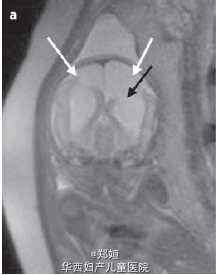

复查超声,提示存活的胎儿脑皮质变薄,怀疑脑穿孔 孕28周MRI检查提示脑穿孔性囊肿 孕41周自然生产3.1kg女婴 胎盘肉眼可见死亡的一胎紧贴胎盘 胎儿MRI提示双侧脑实质局灶性损害 MR造影提示双侧的大脑中动脉阻塞